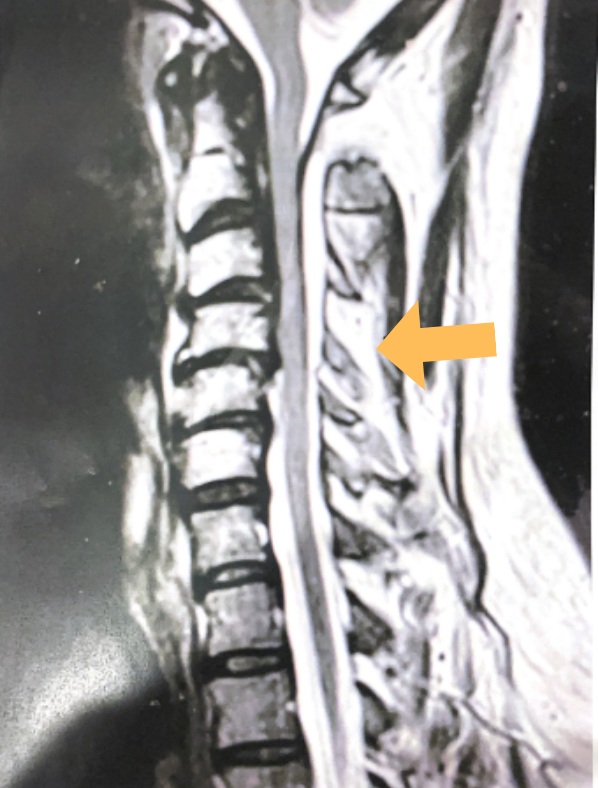

This 57 year-old male presents with severe neck, left shoulder and arm pain and weakness in his hand since being involved in a motor vehicle accident nine months prior. The patient had subsequent left shoulder surgery although he still complained of pain postoperatively and his weakness persisted. He was on no blood thinners. He underwent imaging. The cervical spine MRI revealed an extensive dorsal epidural collection from C1-2 through C5 with associated spinal cord compression. In addition there were multisegmental degenerative changes with foraminal stenosis worse at C4-5 (Fig. 1a and 1b).

(1a) Sagittal and axial T2-weighted cervical MRI demonstrating extensive dorsal epidural collection with hyperintense signal consistent with fluid causing spinal cord compression.

(1b) Hyperintense signal (arrow) at the C3-4 interspinous space consistent with ruptured interspinous ligament,C4-5 (Fig. 1a and 1b).

The fluid was possibly consistent with CSF versus chronic hematoma. The patient was also noted to have a high signal within the interspinous space of C3-C4. This high signal was consistent with a ruptured C3-4 interspinous ligament. Cervical flexion-extension x-rays demonstrated 6 mm of widening of the C3-4 interspinous space on flexion x-ray consistent with cervical instability (Fig. 2a and 2b).